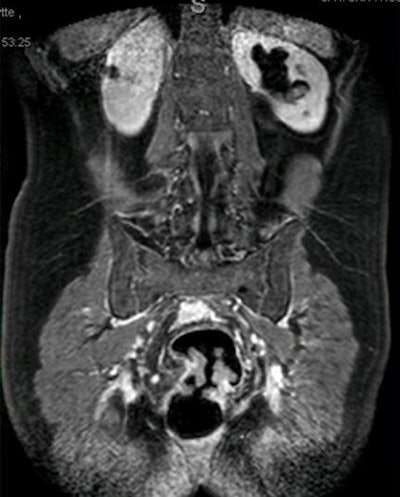

| Obstructing tumor detected at fast dynamic MR colonography. All images courtesy of Michael Achiam. |

The researchers reviewed MRC data acquired over three years to assess whether the use of fast dynamic gadolinium-enhanced MRC could distinguish between benign and malignant colonic strictures, and to demonstrate the feasibility of visualizing the entire colon using MR colonography. The study included a group of patients with endoscopically diagnosed and biopsy-proven benign colon tumor stenosis, along with another group with biopsy-proven obstructive colon carcinoma, who were scheduled for surgery.

Images acquired on a 1.5-tesla scanner (Achieva, Philips Healthcare, Andover, MA) included a T2-weighted balanced fast field-echo sequence, and a 3D T1 turbo field-echo (TFE) sequence following IV administration of 0.2 mL/kg of the contrast agent gadoterate meglumine. A postcontrast scan was acquired approximately 75 seconds later.